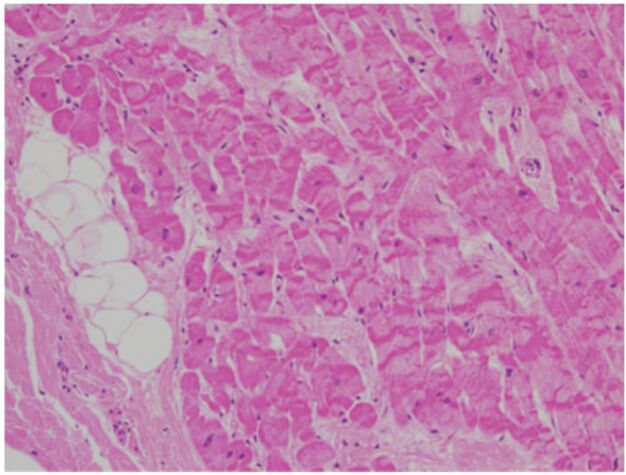

37 一名 58 歲男性在自家後院除草,突然失去意識倒地不起。消防隊員到場急救 30 分鐘後,宣告不治死亡。解剖發現心臟重450 公克,三條冠狀動脈分支都有顯著的動脈粥狀硬化。心臟的病理切片如下圖,下列何者最適合描述它? (A) Contraction band necrosis (B) Myocarditis(心肌炎) (C) Tissue processing artifacts (D) Vasculitis(血管炎)